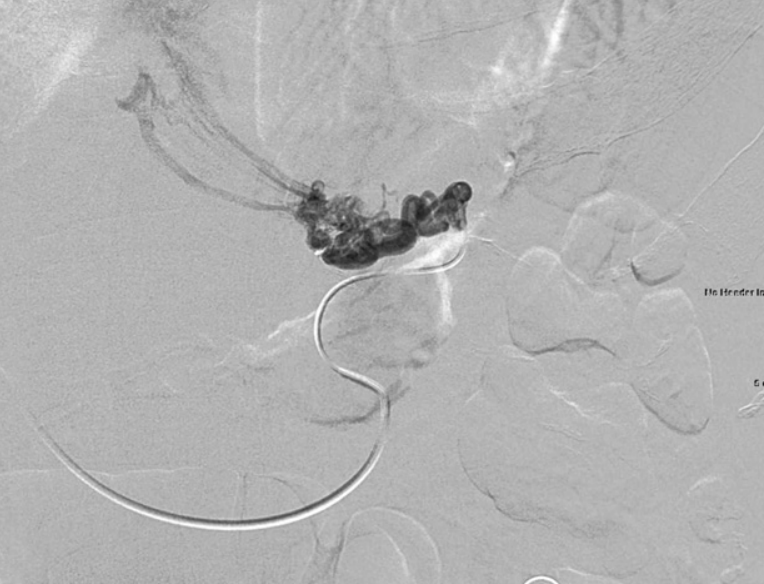

Fig. 4

The remaining gastric variceal flow is well seen on venogram obtained via the other inflow vein of the left gastric vein immediately after glue embolization of one of the inflow veins.